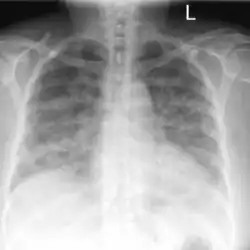

Acute pulmonary edema due to salt water aspiration syndrome

Chest x-rays of a 61-year-old female who developed salt water aspiration syndrome while swimming during a triathlon.[5]

Lung auscultation may reveal abnormal breath sounds such as rhonchi (snoring-like) or crackles (rattling), and chest imaging can show lung consolidations[4] and edema.[5] Decreased lung volumes, including a reduction of average 0.7 liters in forced expiratory volume in 1 second and vital capacity, is found on spirometry. Laboratory studies do not show specific abnormalities, but low oxygen levels in blood, slightly elevated white blood cell count and lactate dehydrogenase levels may be seen.[1]